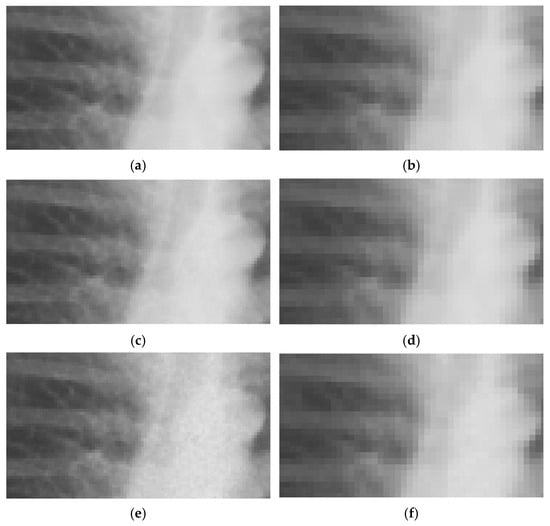

Figure 3. Representative examples of MIMIC-CXR images with different noise levels on training and testing resolutions. LR ((ac): 254 × 305 px), ULR ((df): 127 × 152 px), and normal exposure (a,d); 50% (b,e) and 75% (c,f) simulated dose reductions.

After lowering images resolution to LR and ULR used for CNN input, the noise generated by InGen is less prominent compared to the original full-resolution images, as shown in Figure 3. Note the difference in expression of noise in the examples shown in Figure 2 and Figure 3. SSIM shows comparable results as the full resolution images with all values > 0.998. This indicates a smaller impact of noise on structural similarity. PSNR measurements were higher for lower resolutions, as shown in Table 3, which also indicates a smaller effect of noise on lower resolutions.